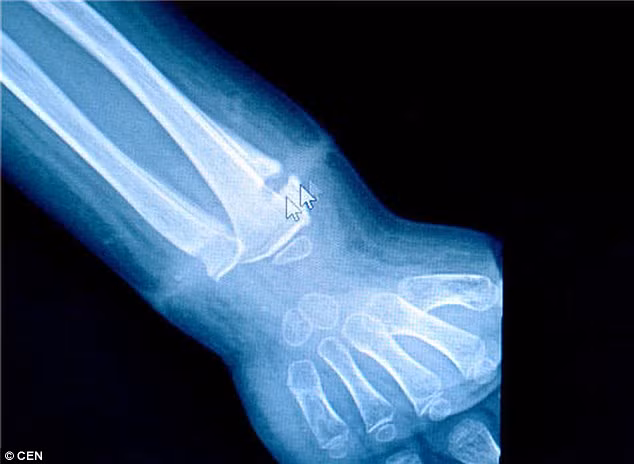

Kết quả chụp X-quang cho thấy chiếc chun đã ảnh hưởng đến phần xương cổ tay khiến bé không thể duỗi thẳng tay trái. “Nếu không kịp thời tháo được chiếc chun ra, Longlong có thể sẽ bị mất đi một phần cánh tay trái” – bác sĩ cho biết. Sau ca phẫu thuật, bé Longlong cũng đã thừa nhận rằng trước đó có đeo chun vào cổ tay nhưng hiện vẫn không xác định được đó là thời điểm nào.